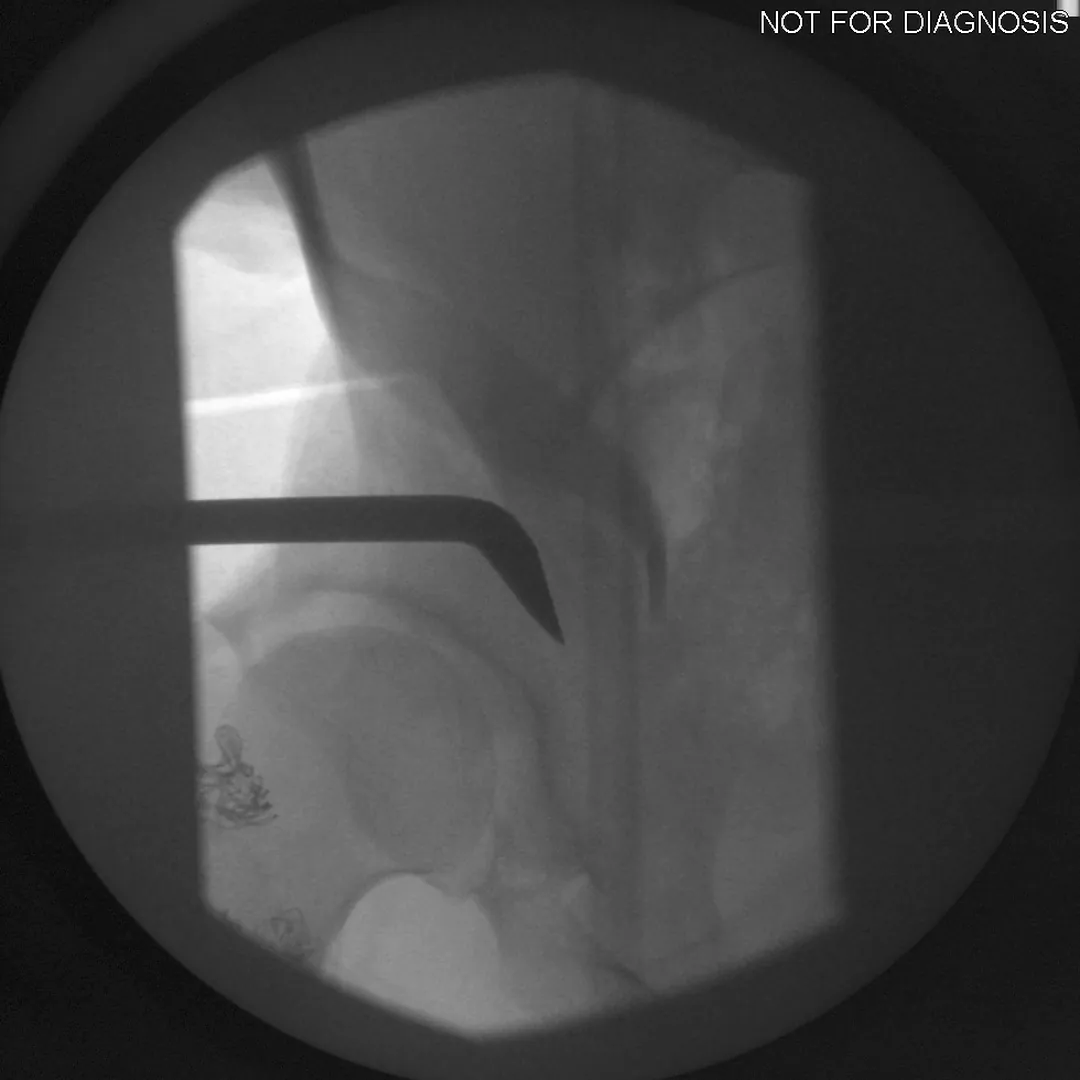

• Several controlled bone cuts are made around the hip socket

• The socket is repositioned and fixed with screws

• The hip joint itself is preserved